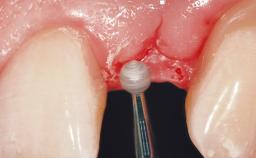

A 33-year-old female patient presented with an upper left central incisor that required extraction after a failed endodontic therapy. The tooth had been traumatized when the patient was a teenager and had undergone several endodontic treatments, including two apicectomy procedures. The patient was in good health and did not smoke. Clinical examination showed that the patient had a high lip line. In full smile, the gingival margins of the upper teeth were visible to the first molars. The gingival margins of central incisors 11 and 21 were only just showing. Examination of tooth 21 confirmed that the tooth was mobile and had hypererupted by 1 mm.

Placement Protocol Immediate implant placement

Tooth Site Maxillary incisor or canine

Socket Morphology Single-root socket